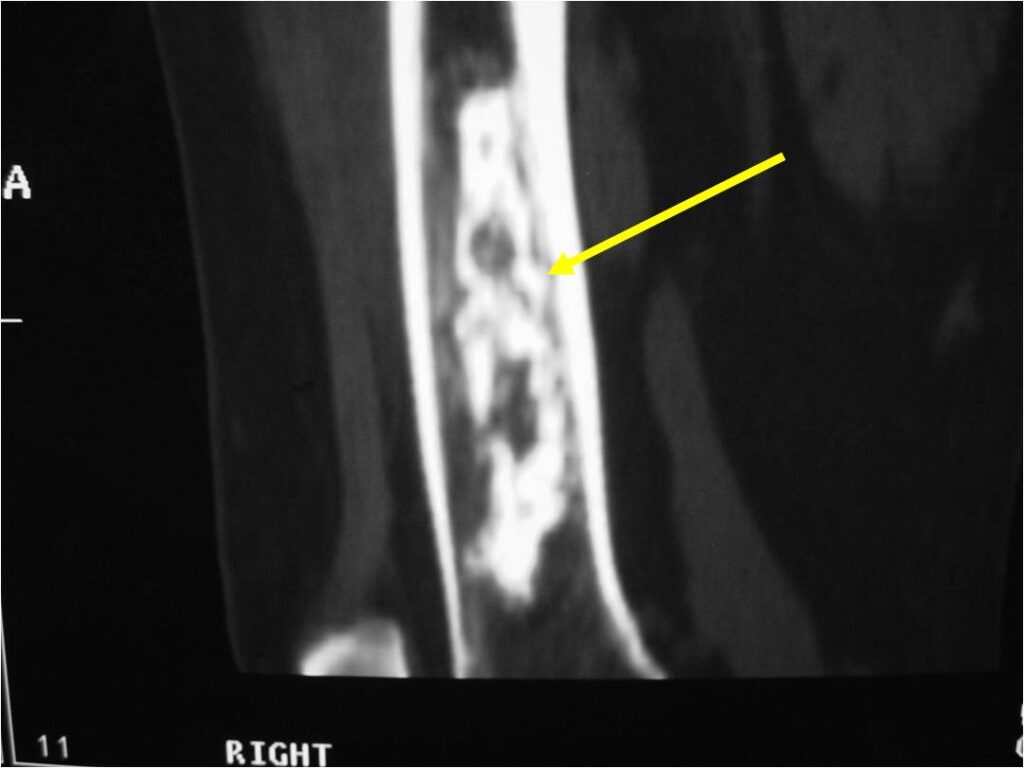

Metaphyseal Tumor, Heavy Calcifications, Ring and Arc Pattern of Calcifications, Minimal Endosteal Scalloping, No Cortical Destruction, No Periosteal Reaction, No Cortical Destruction, No Soft Tissue Component

Metaphyseal Tumor, Heavy Calcifications, Ring and Arc Pattern of Calcifications, Minimal Endosteal Scalloping, No Cortical Destruction, No Periosteal Reaction, No Soft Tissue Component

- There should never be any cortical destruction nor a soft tissue component. If this exists then the tumor must be a chondrosarcoma.

- Endosteal scalloping and cortical expansion is acceptable for phalangeal tumors. In most benign long bone cartilage tumors there is minimal endosteal scalloping but there should be no cortical expansion nor thickening. There should be no cortical destruction and no soft tissue component associated with an enchondroma. Cortical destruction, periosteal thickening, cortical expansion and a soft tissue component indicates a chondrosarcoma of the long bone.